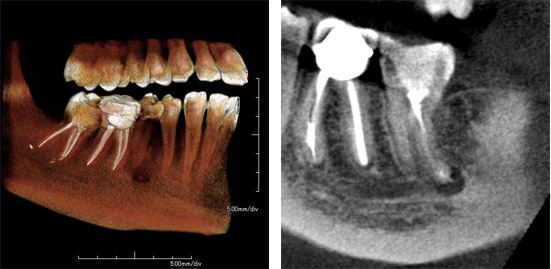

Case1: Root Fracture

The regular 2D x-ray image suggests a possible issue with an endodontic treatment. However, it is not sufficient for a clear diagnosis. The sagittal image of the 3D CBCT scan reveals a root facture.

2D (Dental image) 3DMPR (Sagittal)